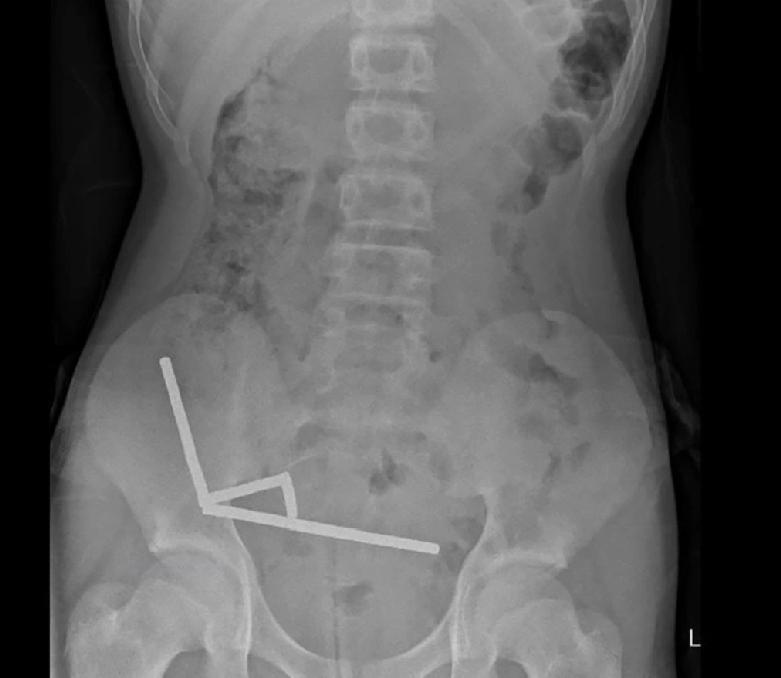

新西兰发生一起离奇医疗案例,一名13岁少年吞下多达100块从中国电商平台Temu购买的强力磁铁,腹痛难忍就医。外科医生发现少年有4处组织坏死,需手术切除部分肠道。 X光片曝光,惊现4条长直链 据报道,这名未透露姓名的少年吞下磁铁后腹痛4天,随后被送往新西兰北岛的陶朗加医院(Tauranga Hospital)治疗。X光片显示,磁铁在少年肠道不同位置因磁力吸附在一起,形成4条长直链。